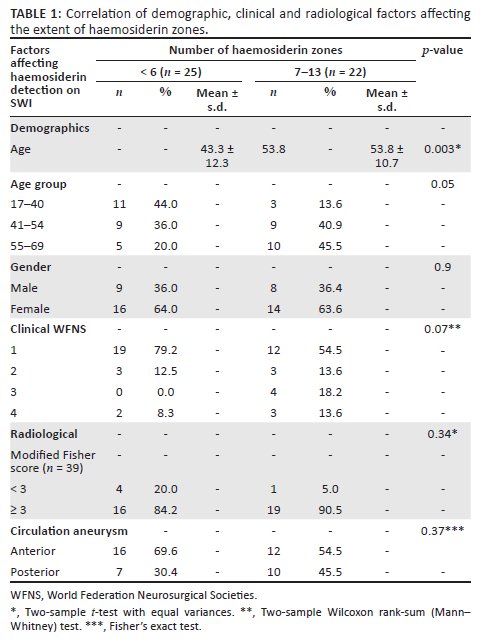

Demographic data relating to haemosiderin zones are presented in Table 1. Females represented 63% (n = 29) of patients. The median age was 49 years (range 17-69 years). A statistically significant correlation was identified between increasing number of haemosiderin zones and increasing age (p = 0.003). No relationship was found between gender and the number of haemosiderin zones.

There was a tendency towards a higher number of haemosiderin zones having higher initial clinical severity, WFNS; however, not reaching statistical significance (p = 0.07). Five patients had a modified Fisher score < 3 and 34 patients had modified Fisher scores of 3-4. No statistical significance was found between the number of haemosiderin zones and the type of circulation aneurysm (p = 0.37) or the modified Fisher score (p = 0.34).

Secondary objectives of the study were to evaluate for any correlations between the number of haemosiderin-stained zones with patient demographics, location of the causative aneurysm, initial clinical (WFNS) or radiological severity (modified Fisher score).

Demographics

Studies performed by Imaizumi et al. and Falter et al. showed no statistical significance between age and haemosiderin extent on T2* imaging. However, previous researchers have shown that age had a statistically significant relationship with the presence of haemosiderin on T2* GE imaging (p = 0.02).12,13,14 Like previous studies it is hypothesised that with ageing and subsequent cerebral atrophy there are larger subarachnoid spaces, which allow for larger areas of haemorrhage aggregation and hence haemosiderin deposition.12 The current study concurred with Lummel et al. indicating a statistically significant correlation with increasing numbers of haemosiderin deposition zones and increasing patient age (p = 0.003).

Aneurysmal subarachnoid haemorrhage has a 50% increased incidence in the female population. Previous studies utilising T2* by Imaizumi et al. and Falter et al. demonstrated no statistically significant correlation between gender and the extent of haemosiderin staining. Similar findings were found in this study with females representing 63% of the study population and no statistical correlation with the number of haemosiderin zones (p = 0.9).

Clinical Severity World Federation Neurosurgical Societies Score

Falter et al. identified a statistically significant relationship between initial WFNS and the extent of haemosiderin staining on T2* imaging (p = 0.0008).12 This study showed an approaching tendency (p = 0.07) between the number of haemosiderin zones and WFNS, but was not statistically significant. The clinical applications imply that haemosiderin detection on SWI in the chronic phase may infer a more clinically severe initial ASAH (clinical WFNS grade).

Radiological severity (modified Fisher Score)

Modified Fisher scale on initial NECT has been proven to correlate with vasospasm risk. The mechanism is related to the direct effect of haemorrhage on the vessels in the subarachnoid space.20 Imaizumi et al. divided the cerebral convexities into 10 zones and imaged ASAH in the chronic phase. Their findings showed that ≥ 4 haemosiderin zones correlated with an initial modified Fisher score of ≥ 3 (p = 0.0005). Falter et al. and Lummel et al. showed that T2* had corresponding statistically significant findings where a modified Fisher score ≥ 3 correlated with the presence of haemosiderin (p = 0.0004 and p = 0.03, respectively).12,14 The mechanism is postulated to be related to the larger initial haemorrhage load resulting in greater haemosiderin staining and hence detection on imaging in the chronic phase. The current study showed no statistically significant correlation (p = 0.34). This could be because of SWI's increased sensitivity to detect small amounts of haemosiderin and thus haemosiderin remotely located from the initial rupture, even in small initial haemorrhage loads (lower modified Fisher scores). As a result of the inherent limitations of this study with a bias of patients with higher modified Fisher scores ≥ 3 (n = 35) and underrepresentation of lower modified Fisher scores < 3 (n = 5), a true statistical analysis is limited.